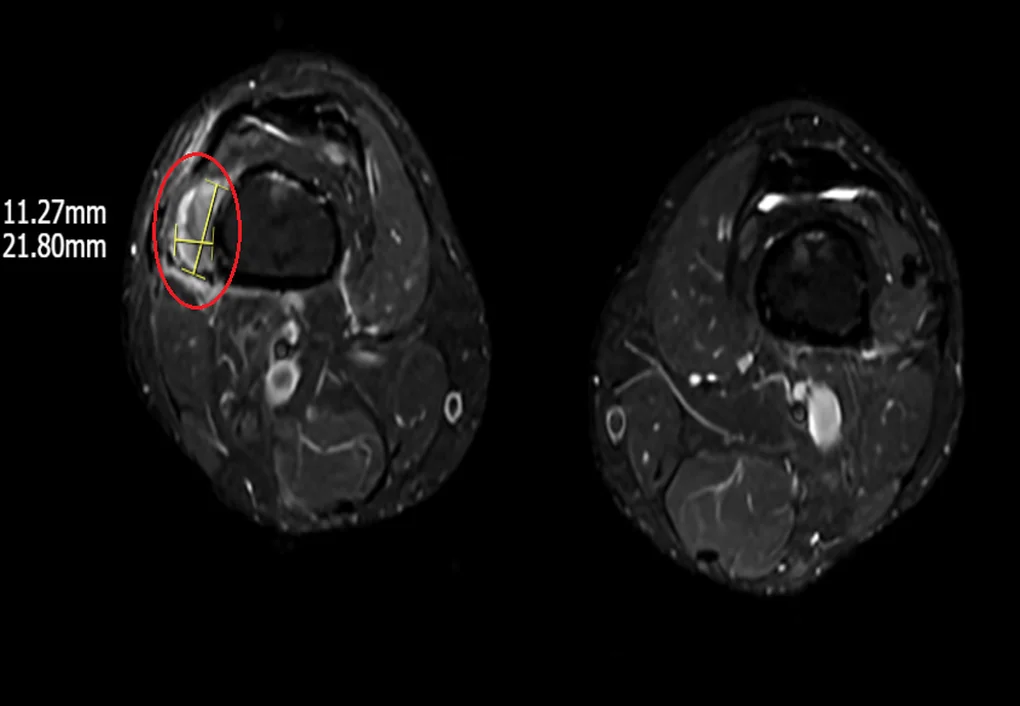

Hình ảnh khối u vùng vị trí phần mềm dưới đùi phải trên phim MRI (Ảnh: BVCC).

“Việc cần làm là phải xác định được vị trí của khối u để loại bỏ triệt để căn nguyên gây thiếu hụt phốt pho khiến xương giòn yếu. Tuy nhiên, thách thức của quá trình chẩn đoán là u tăng tiết FGF23 thường là u lành tính, nhỏ, không sưng đau và có thể ở xuất hiện ở bất kỳ vị trí nào trên cơ thể.

Để củng cố chẩn đoán bệnh cần phải định lượng chỉ số FGF23 trong máu, tuy nhiên, ở Việt Nam hiện chưa có xét nghiệm này. Do đó, chúng tôi chỉ định bệnh nhân chụp PET/CT toàn thân với chất phóng xạ kết hợp chụp MRI, siêu âm, cuối cùng tìm thấy 1 khối u kích thước 1-2cm vị trí phần mềm dưới đùi phải”, ThS.BSNT Vân chia sẻ.